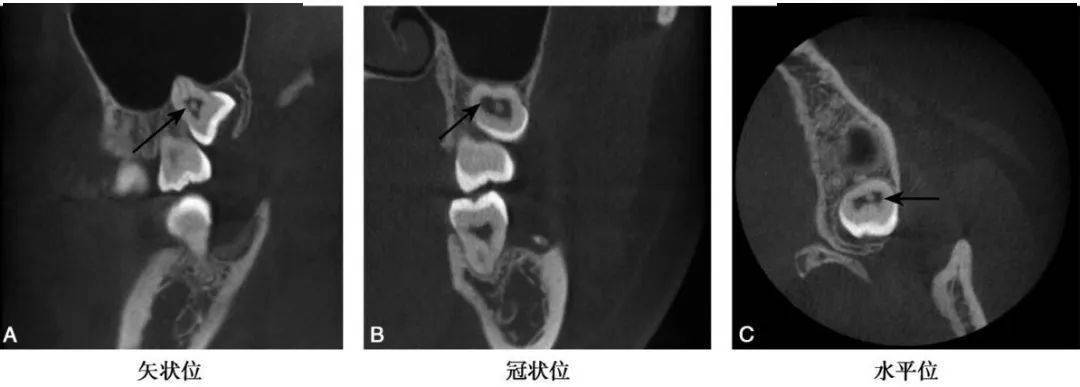

图1 B8髓腔髓石CBCT示B8髓腔内见一类圆形高密度阻射影(黑色箭头)

(1)髓石在髓腔中表现为不同形状的高密度团块影,形态与髓腔的形状有一定关系,后牙髓腔中的髓石可为圆形、卵圆形或不规则形(图1~3)bccbch币。